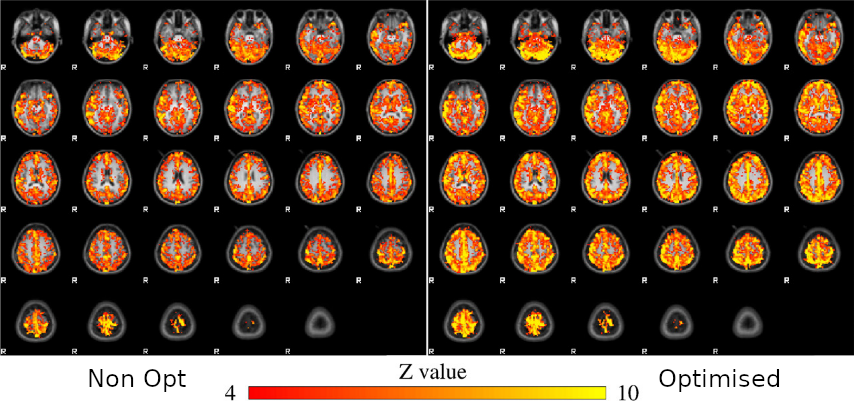

Results: model comparison

Moia et al. 2021 (NeuroImage)

CVR amplitude

CVR lag

CVR amplitude

CVR lag

Results: model comparison

Moia et al. 2021 (NeuroImage)

CVR amplitude

CVR lag

CVR amplitude

CVR lag

Results: model comparison

Moia et al. 2021 (NeuroImage)

Reliability [ICC (2,1)]

Moia et al. 2021 (NeuroImage)